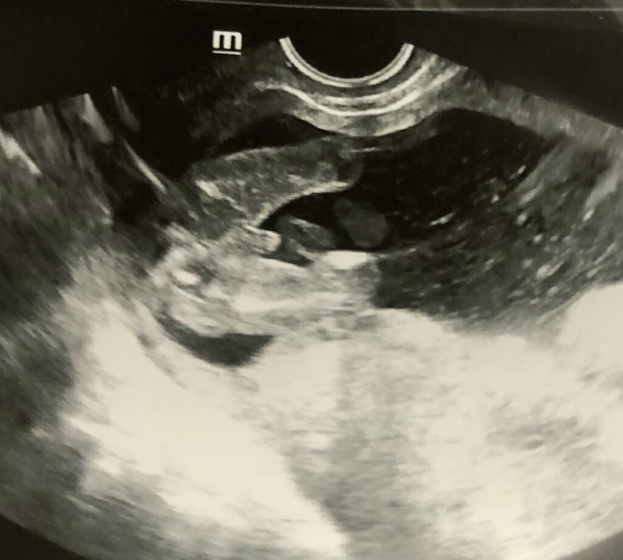

Добрый вечер) 16 неделя

Девчонки, как думаете что это болтается на фото ?

Большие половые губы, яички (писюн) или пуповина? ?

Если яички или писюн, то я не понимаю что это именно. Лежит как-то в сторону, диагональю. Не видела таких узи.

Мне кажется пуповина, идёт чёткое продолжение дальше....

Мне кажется пуповина. Уж какое-то очень большое для 16 недель достоинство.

Это писюн, яички позже спускаются в мошонку. Это не пуповина

Где какие яички? Мазня какая то, даже ребенка не разбираю.